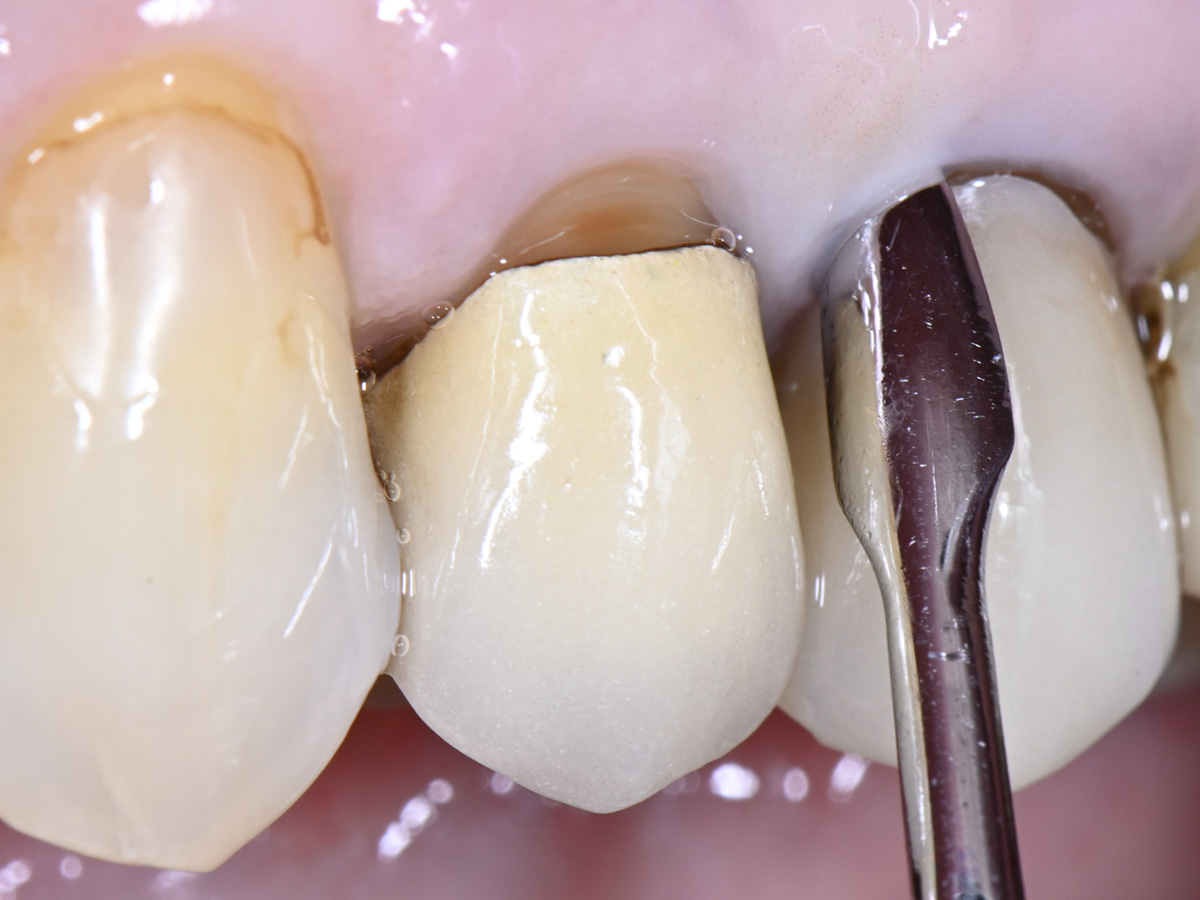

Abbildung 3

Intrasulkuläre Inzision um den nicht erhaltungswürdigen Zahn mit der Micro Blade SR